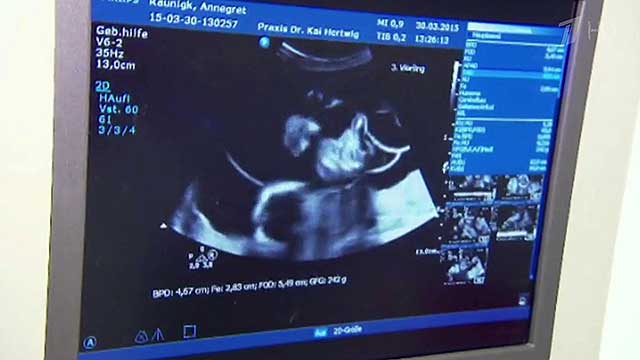

Пенсионерка в Германии родила сразу четверых детей

65-летняя женщина в Германии Аннегрет Раунинг родила сразу 4 малышей и, вероятно, установила мировой рекорд среди «возрастных» рожениц. Помимо 4-х новорожденных, пенсионерка имеет еще 13 детей и 7 внуков.

Как сообщает источник, четверо детей родились немного раньше срока. Трое мальчиков и одна девочка весили на момент родов меньше килограмма и сейчас находятся в больнице в специальных кювезах под наблюдением врачей.